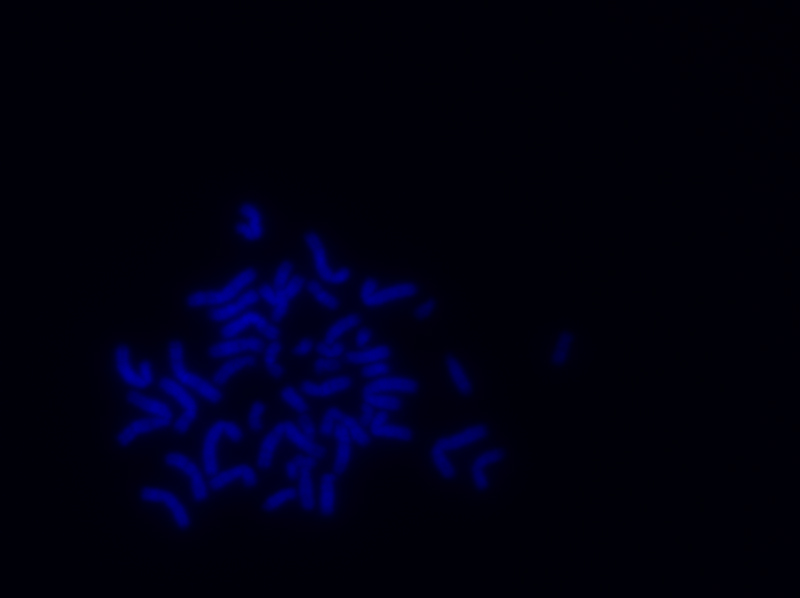

My chromosomes from DNA ouputs from lab for DNA sequencing 2003 used for Stanza art experiment.